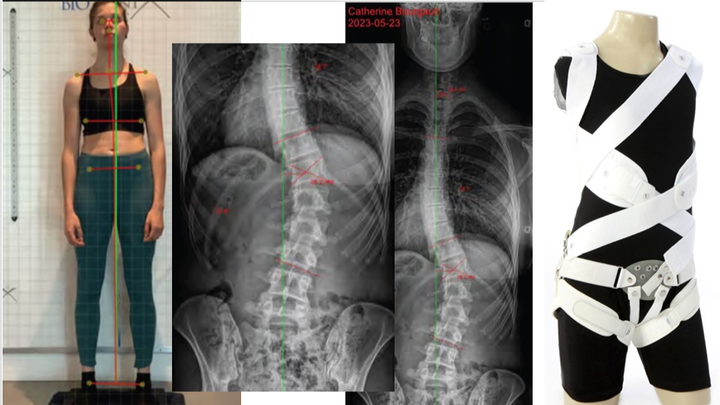

La source du problème, une scoliose idiopathique de 43 degrés (déformation tridimensionnelle de la colonne vertébrale). À 20 ans, on me parlait d'invalidité, j'ai pris du recul et fait beaucoup de travail psychologique (et d'aquaforme hihi) afin de me permettre de reprendre le sport, mais surtout de retrouver un certain confort au quotidien. Or, la dernière année a été particulière ardue, mes douleurs se sont propagées pour la première fois dans toute ma jambe droite, affectant l'usage de celle-ci et m'obligeant à arrêter tout effort physique (douleurs neurologiques causées par ma scoliose qui provoque un effondrement de disque vertébral). Je ne réussis toujours pas après 9 mois de traitement à retrouver un niveau de contrôle sur ma douleur dont j'avais acquis dans les dernières années, niveau qui me permettait de faire du sport et mes tâches quotidiennes.

Après plusieurs semaines de réflexion, j'ai décidé de consulter une spécialiste en scoliose qui me recommande l'achat d'un corset dynamique de correction pour limiter les impacts de mes déviations (sténose et arthrose principalement). Or, le corset à lui seul se vend 4750$ (non couvert), en plus d'un protocole de soins pour les prochains mois qui me coûtera près de 5 000$ (j'ai déjà atteint le montant de 900$ en 1 mois en consultations/ajustements avec la spécialiste, pour vous donner une petite idée). Vous comprendrez que le 300$ couvert par mes assurances par année avait déjà été largement dépassé, avant même d'être référée à cette spécialiste, car depuis janvier 2023 seulement, mes frais de santé ont atteint 2155$.